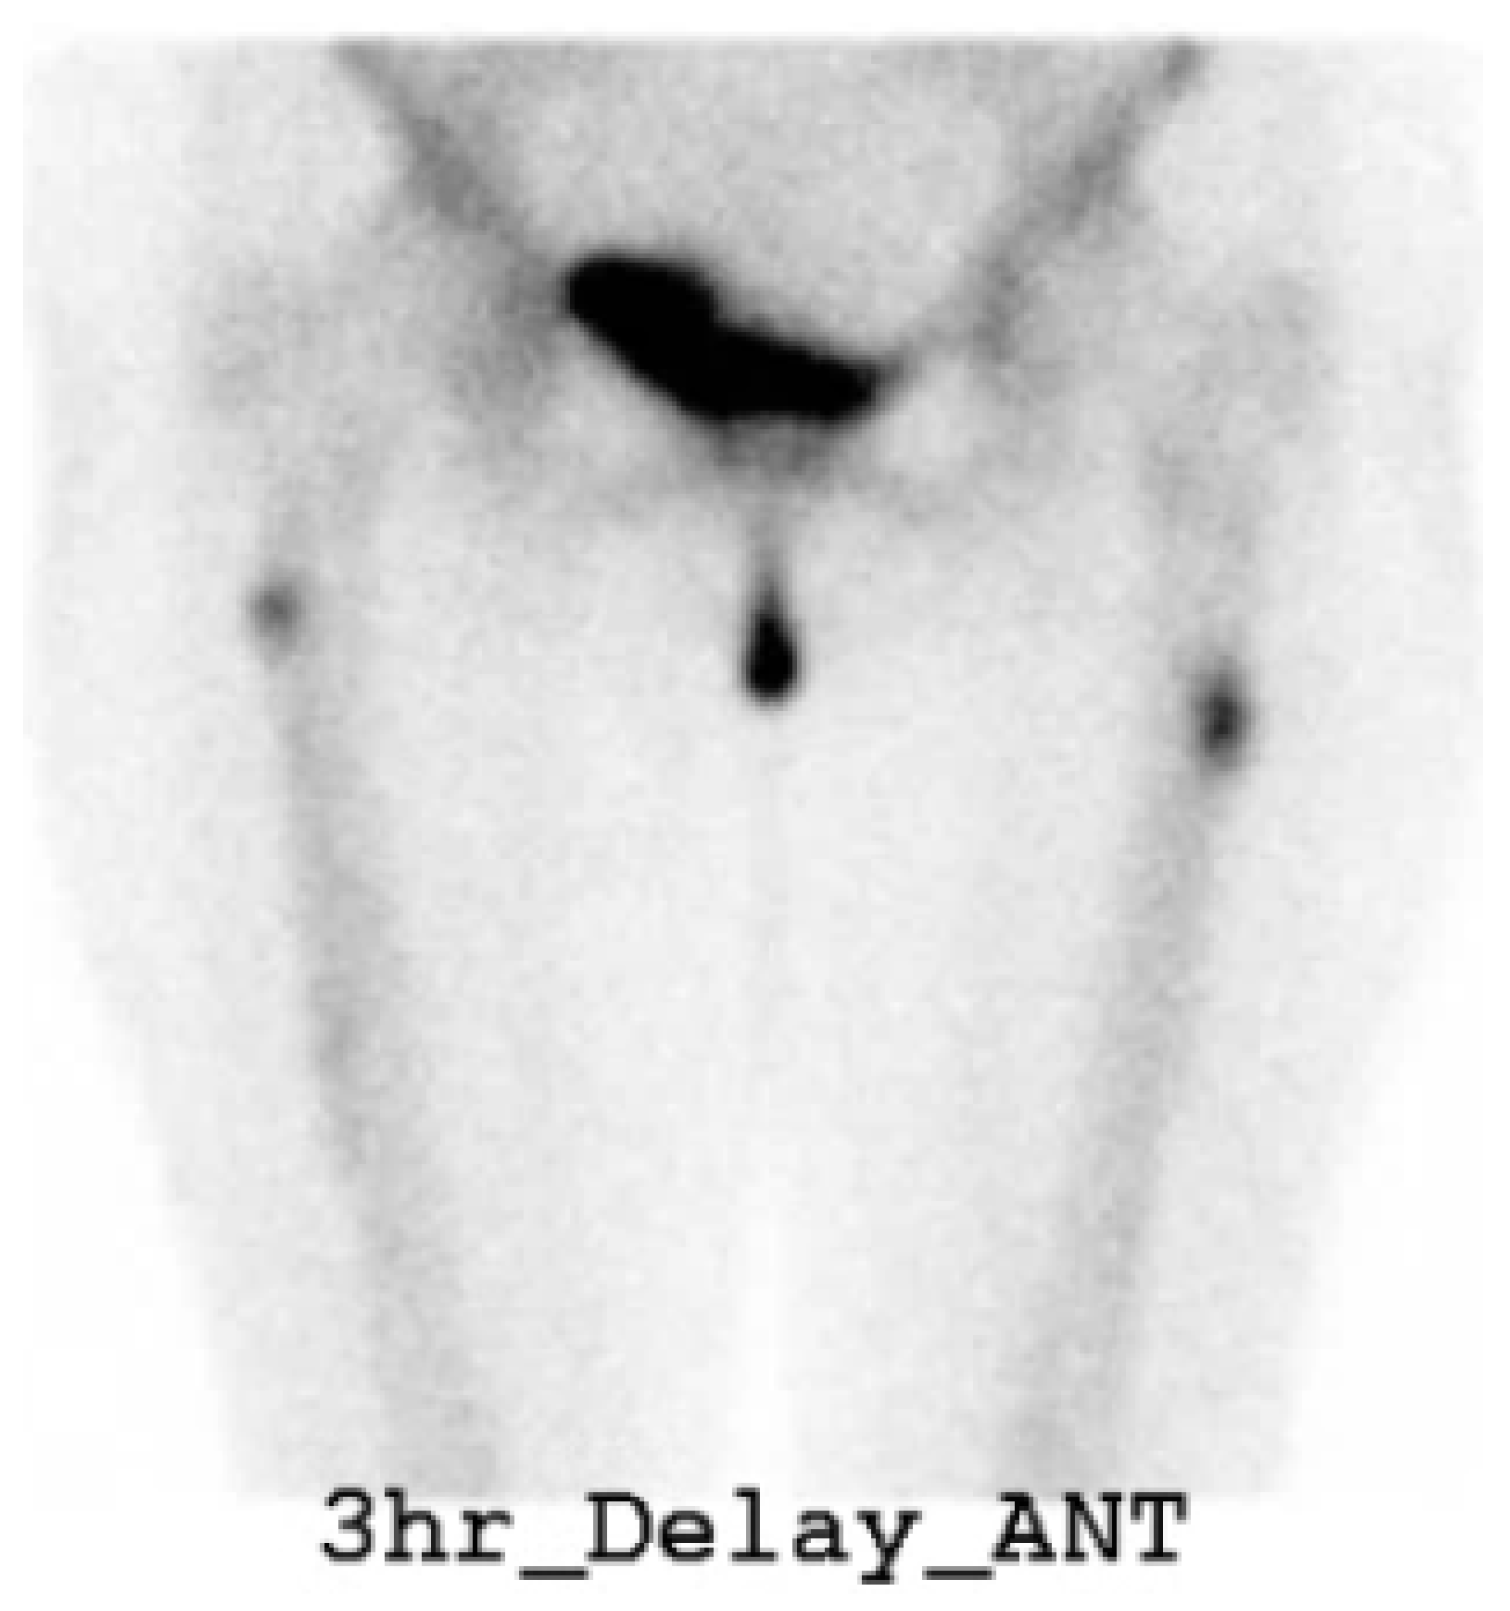

- Kim, J.E.; Yun, M.; Lim, S.-K.; Rhee, Y. Concurrent bisphosphonate-related bilateral atypical subtrochanteric fractures and osteonecrosis of the jaw on bone scintigraphy. Clin. Nucl. Med. 2015, 40, 450–452. [Google Scholar] [CrossRef]

| 26 | Jo Eun Kim et al., 2015 [30] | F, 82 | O/O | Sequential (2 years) | Unknown BP for 7 years | Prox/prox | PIM nailing/X | NA | NA |